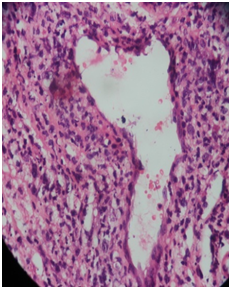

Finally the patient underwent wide local excision of the lesion and overlying necrosed skin under general anesthesia presuming it to be a pseudo tumor with super imposed fungal infection. The specimen was sent for histopathological and immunohisto chemical analysis. The H&E stained sections showed extensive necrosis, areas of hemorrhage, prominent blood vessels and multifocal cellular infiltration (Figure 4). Some of the vessels were thrombosed, and showed perivascular coagulative necrosis. The major cellular component was atypical lymphoid cells with evidence of super imposed fungal infection.

Figure 4 Showed extensive necrosis, areas of hemorrhage, prominent blood vessels and multifocal cellular infiltration.